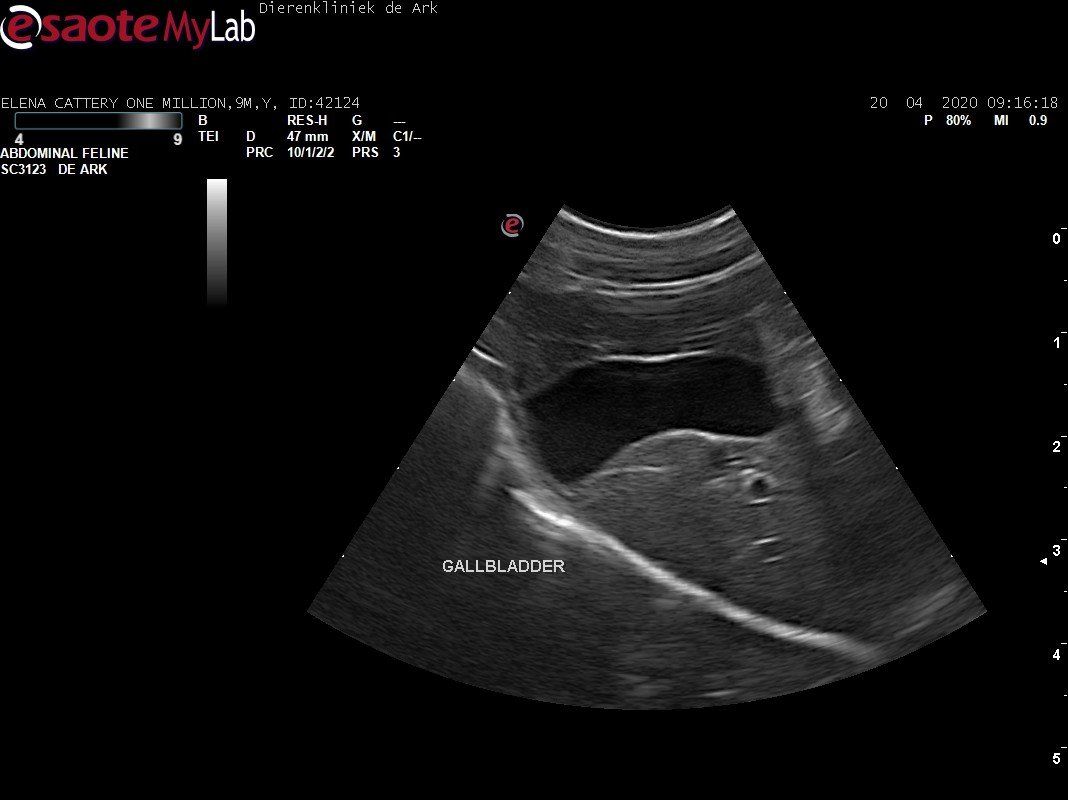

3,200 kg , echo en nieuw bloedonderzoek gedaan wat perfect ging door middel van gapabetine

Voor de garanties en om recht te hebben op medicatie bij herval eist Mutian diverse onderzoeken en controle momenten. Dit zijn bloedonderzoeken maar ook zoals hieronder te zien is echo's. Elana is volledig gecontroleerd op afwijkingen, gelukkig waren de echo's goed.